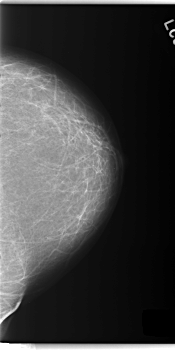

C_0143_1.LEFT_MLO

LEFT_MLO LINES 5872 PIXELS_PER_LINE 3096 BITS_PER_PIXEL 12 RESOLUTION 50 NON_OVERLAY